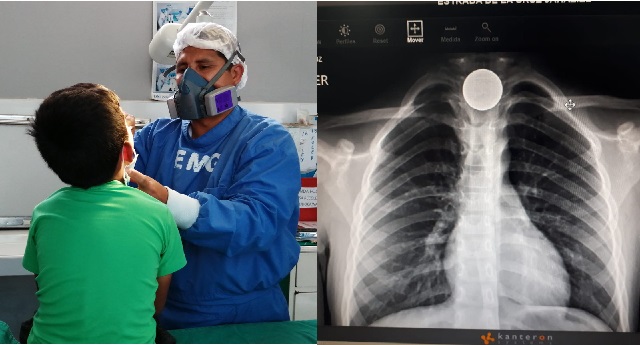

Huaraz en Línea. - Después de varios meses de haber estado suspendida las cirugías oncológicas en el Hospital Regional E...